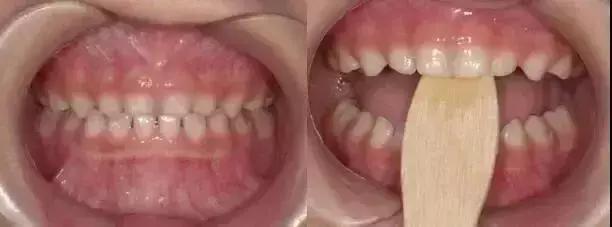

02、咬撬法

没得错,就是喊你咬棍棍儿!选择压舌板或牙刷柄,每天咬撬木板三次,每次大约2分钟(约20下),每两周复诊,1-3个月就阔以有效纠正“地包天”。